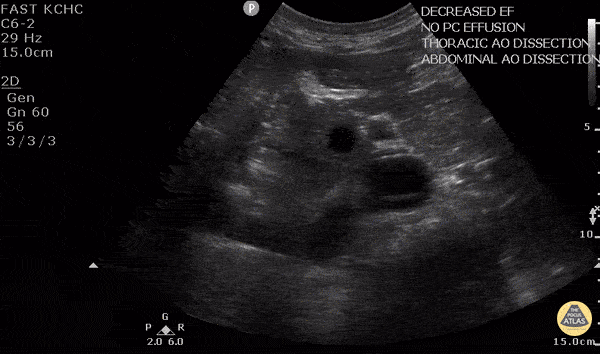

Aorta - Aortic Dissection

50 y/o M w/ hx of HTN p/w sudden onset upper back pain. POCUS found dissection flap in the descending aorta in both parasternal long view and abdominal aorta. The diagnosis of aortic dissection was quickly confirmed by CT. Given the importance of timely diagnosis with aortic dissection, POCUS allowed rapid and non-invasive diagnosis of a potentially tricky diagnosis, and facilitated expedited treatment and transfer to a cardiothoracic surgery center. Dr. Robert Allen - Kings County Emergency Medicine